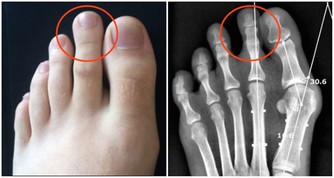

二為手足心多汗

如果手足心多汗伴有手腳心熱、口咽乾燥等,多屬於陰虛有熱;若手足心多汗伴隨腹部脹滿疼痛,大便不通,多屬於腸道內有積糞的熱證,可服用通便藥。